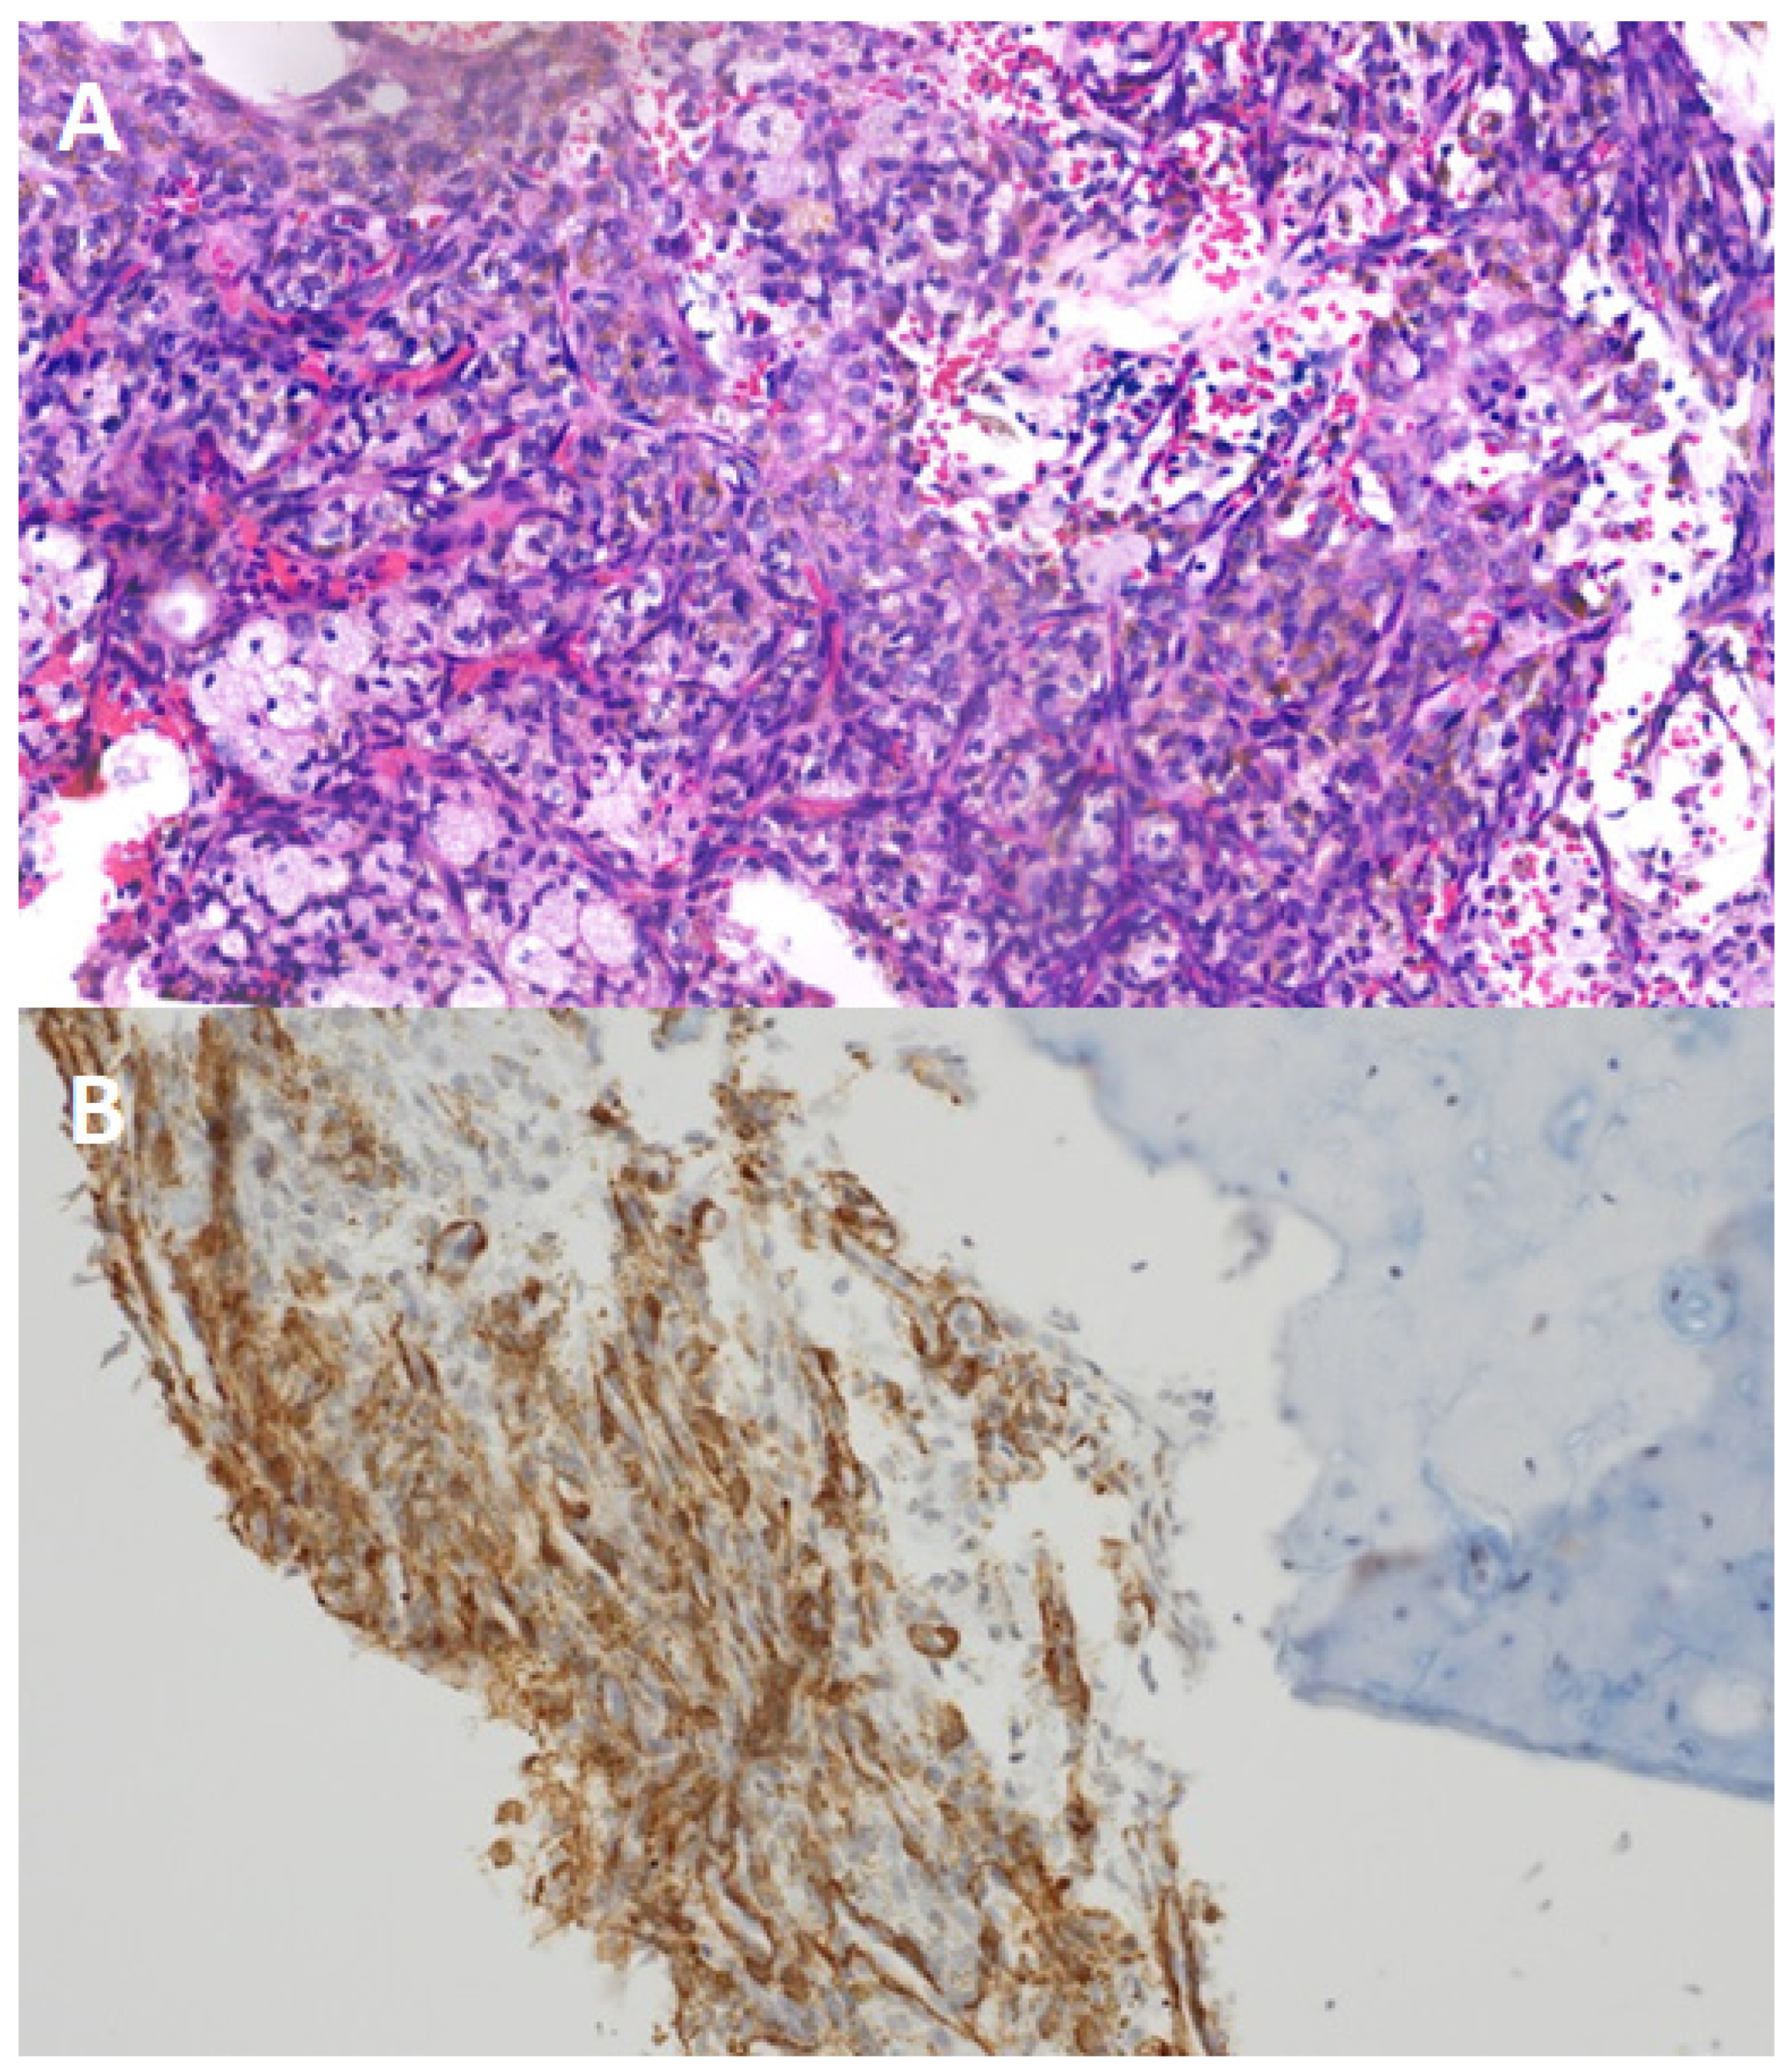

Figure 2. Panel (A): histological analysis of the excised lesion revealed histiocytes, siderophages, cholesterol crystals, and spindle cell proliferation without malignancy markers. Panel (B): immunohistochemical tests showed EMA, S100, and creatinine negativity but SMA positivity, confirming a benign fibrous histiocytoma.